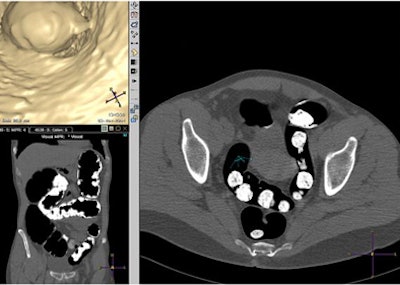

![]() |

| Axial multiplanar reformatted coronal and endoluminal 3D images show subjective evaluation in four different patients with various grades of fecal tagging. Above, in 51-year-old woman with history of colorectal polyps, reviewer evaluated fecal tagging as good. Image republished with permission of the American Roentgen Ray Society. Jensch S, de Vries AH, Pot D, et al. Image quality and patient acceptance of four regimens with different amounts of mild laxatives for CT colonography. AJR. 2008;191(1):158-167. |